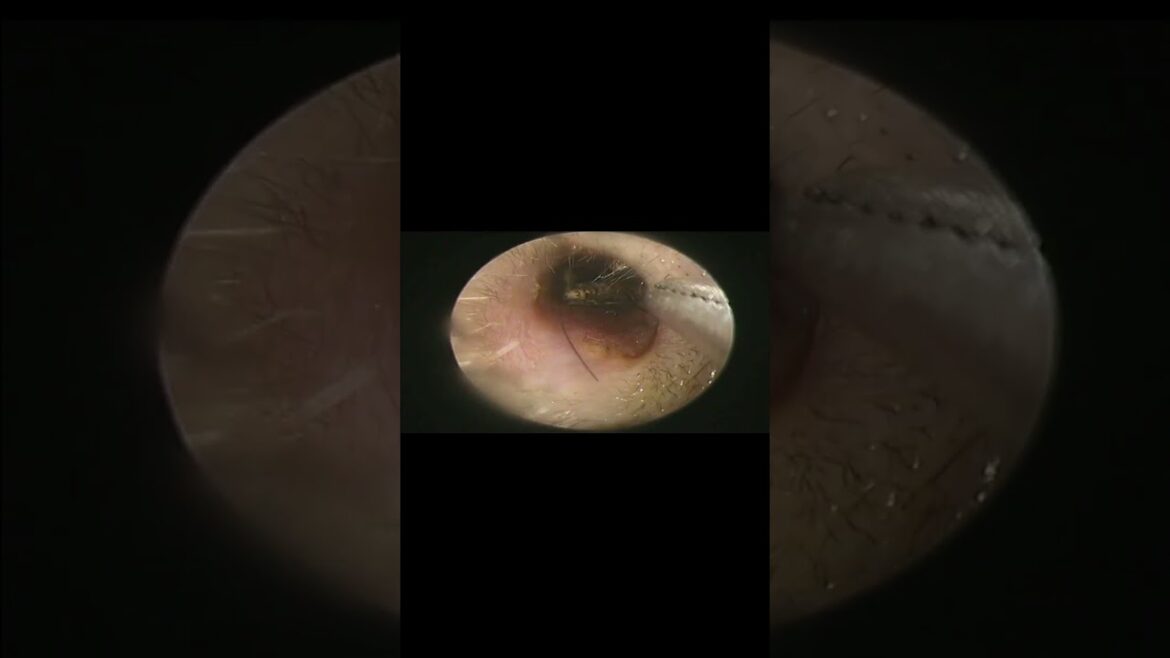

The foreign object is an insect that has been in the ear for 1 month. The patient was examined and the foreign object removed from the ear by Doctor Anh